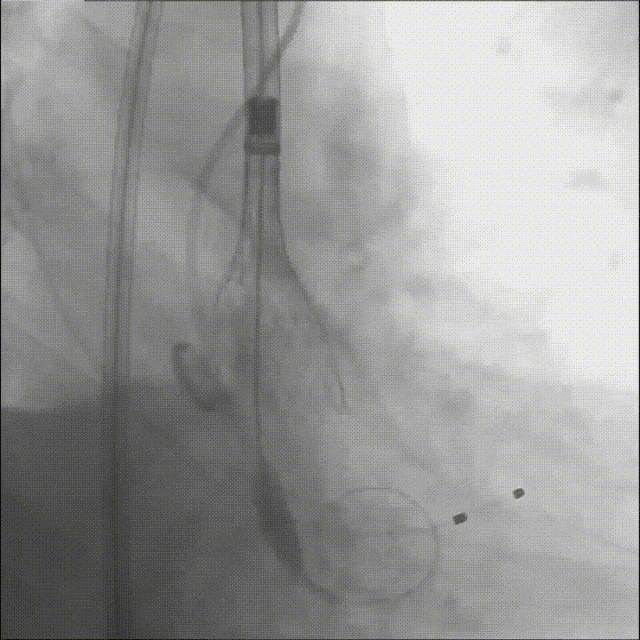

瓣膜释放后造影及食道超声评估可见瓣膜释放形态欠佳,可见瓣周漏,并发现右冠开口血流缓慢,高度警惕右冠灌注障碍;

瓣膜释放后造影

在保护右冠的前提下,精确释放开窗支架,恢复右冠灌注,随后行球囊后扩确保瓣膜贴壁充分,兼顾瓣膜功能与冠脉通畅;

右冠保护下球囊后扩